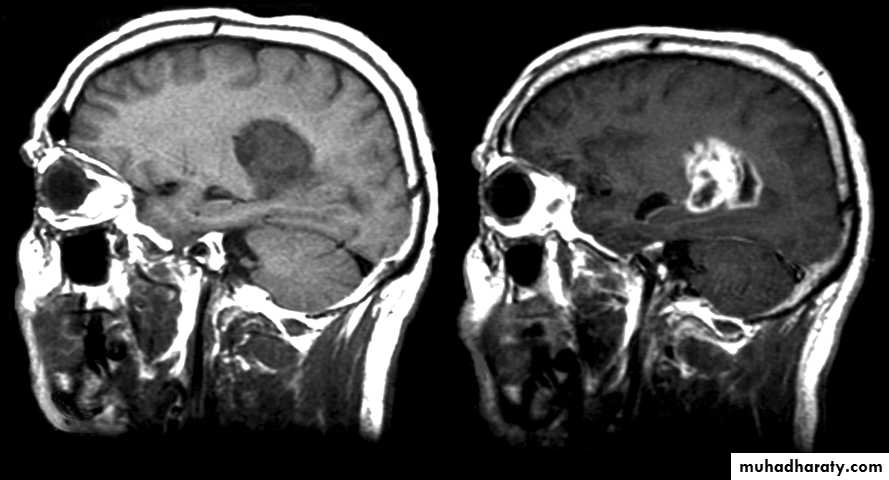

Magnetic Resonance Imaging

• MRI uses the magnetic properties of spinning hydrogen atoms to produce images.

Applications of MRI:

• Imaging modality of choice for most brain and spine disorders• Musculoskeletal disorders, including internal derangements of joints and staging of musculoskeletal tumors

• Excellent soft tissue contrast and characterization

• Lack of artefact from adjacent bones, e.g. pituitary fossa

• Multiplanar capabilities

• Lack of ionizing radiation.